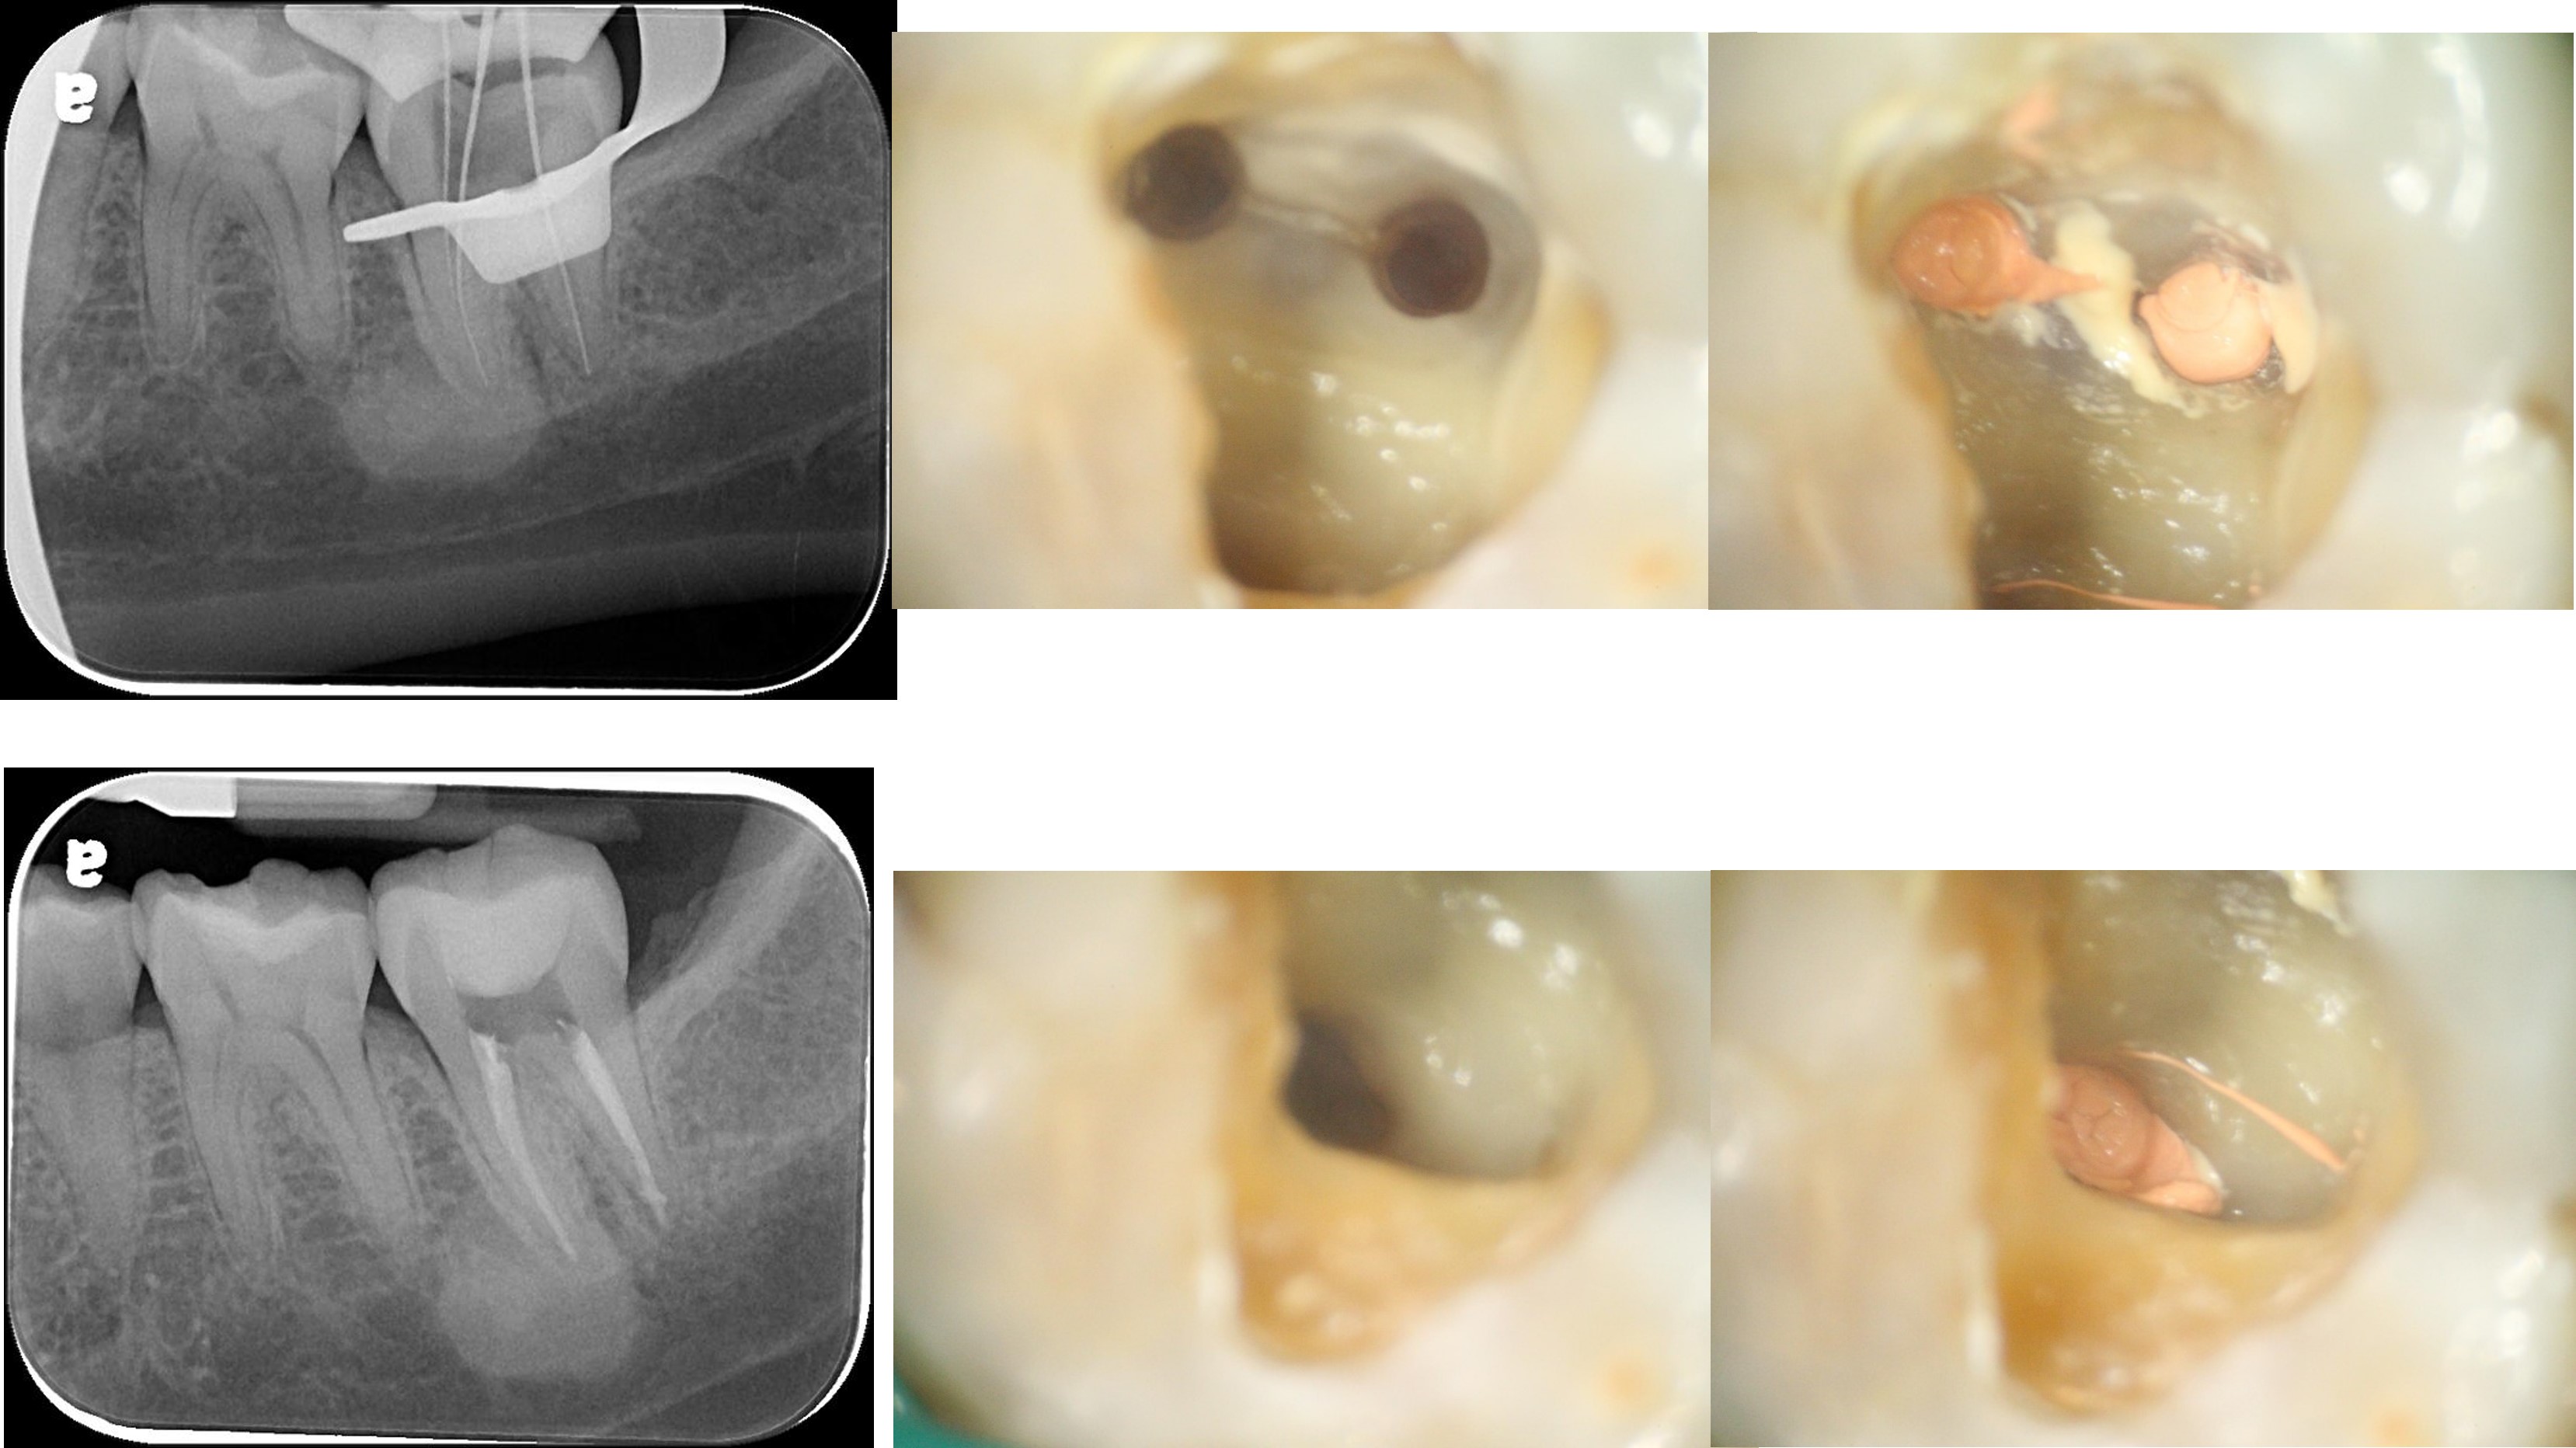

冠塊體牙齒製備